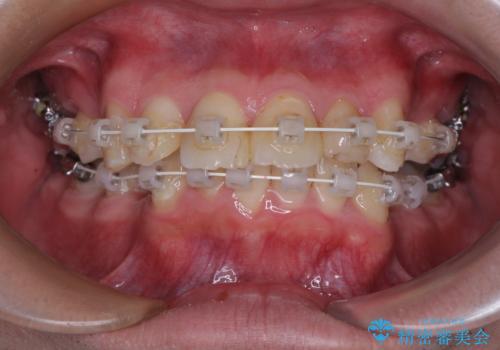

【モニター】出っ歯と奥歯の咬み合わせを改善 補助装置を用いたワイヤー抜歯矯正

- 審美装置

- 口元の突出感と奥歯の咬み合わせの悪さを気にして来院された患者様です。

口元はやや突出感があったため、上下左右の第一小臼歯4本を抜歯してワイヤー矯正にて抜歯矯正を行うこととしました。

また、左右ともに最後臼歯が交叉咬合になっており、外側に飛び出している上顎の最後臼歯を補助装置を利用して、積極的に内側に引き込むようにしました。

2年半の治療期間を想定しており、予定通りの期間で無事に終了することができました。

唇や顎先に力を入れないなくてもスムーズに唇を閉じることができるようになりました。